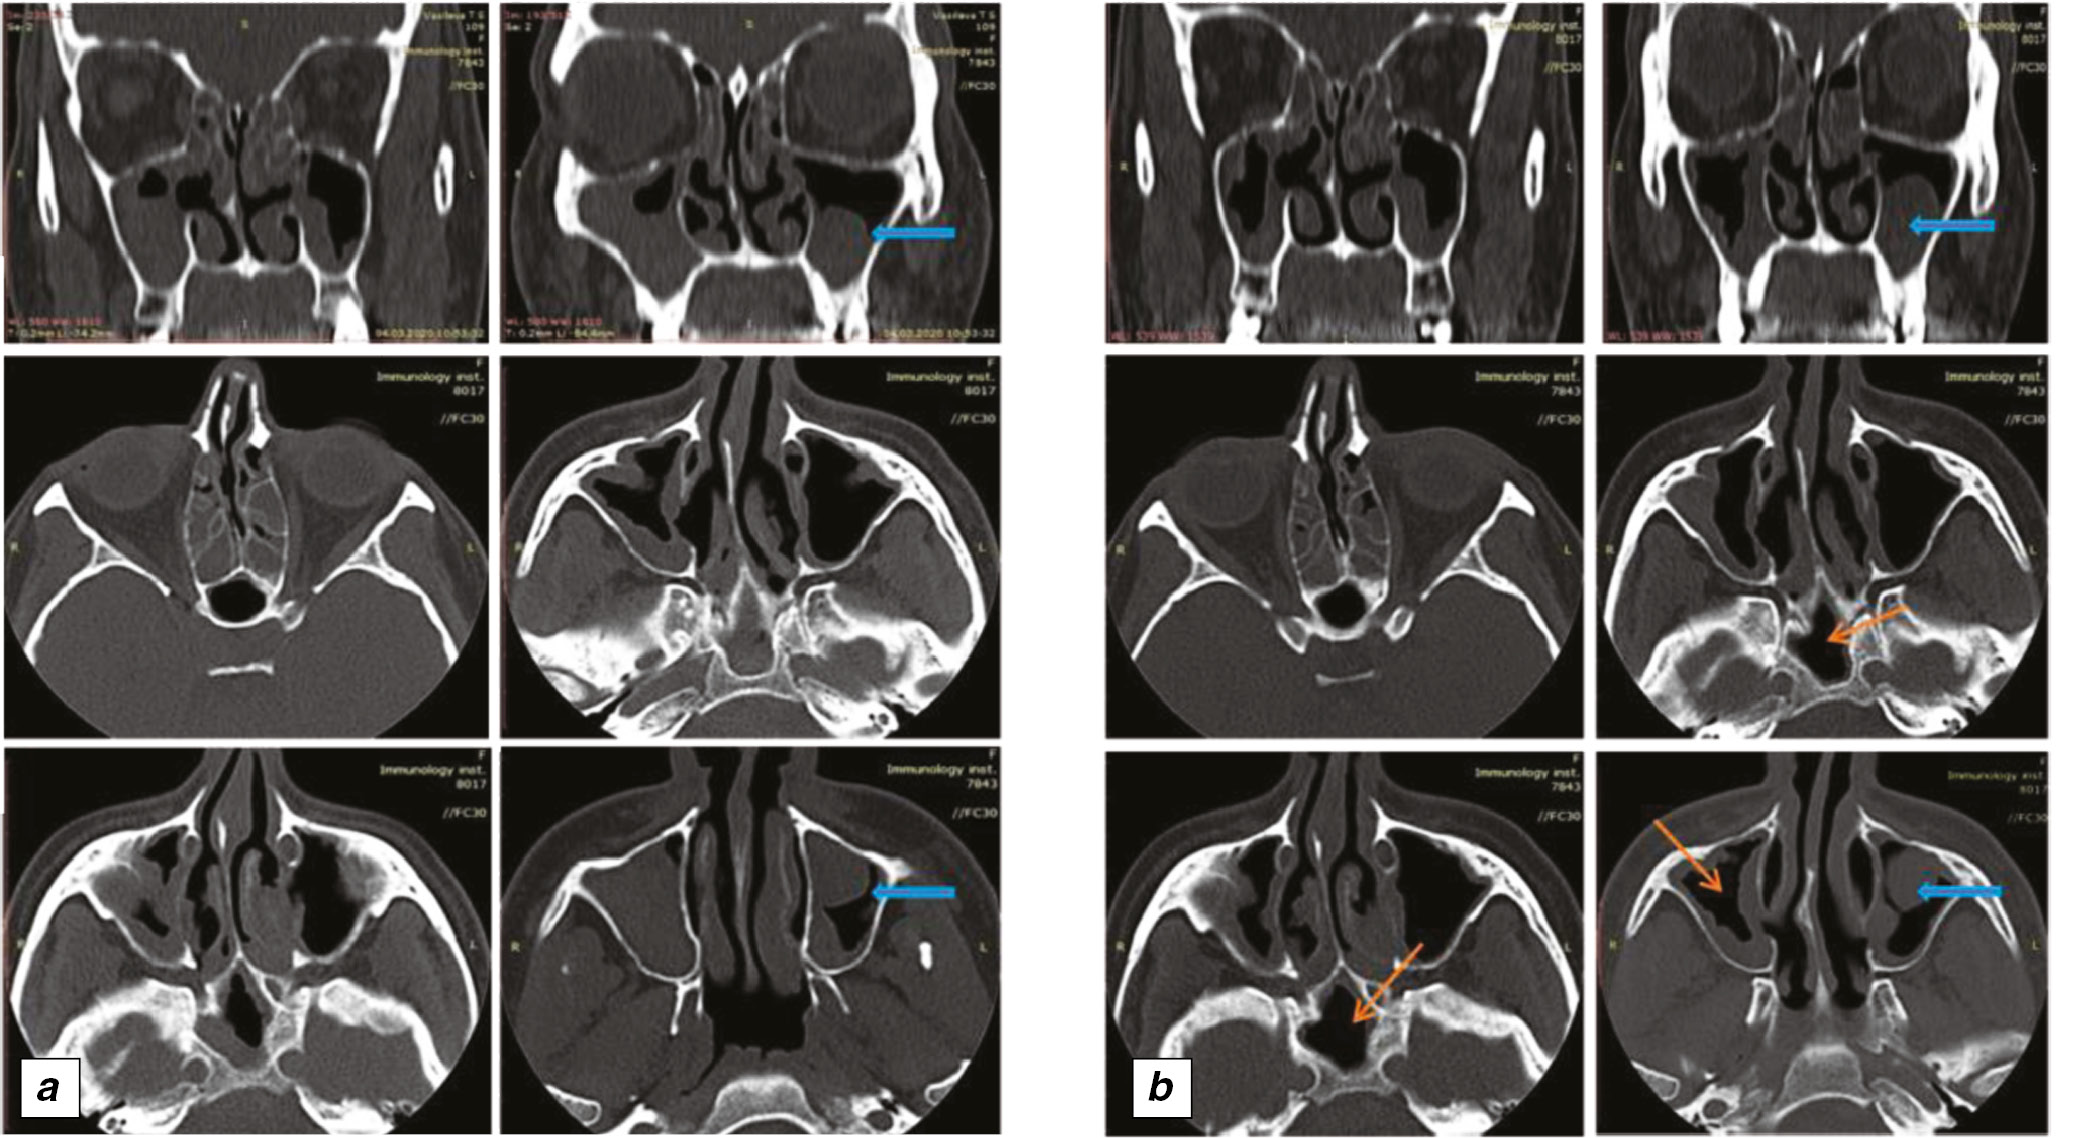

As for CRSwNP, its course improved since the nasal congestion and the need for topical GCs decreased. After one month of treatment, the patient noted the ability to smell. ENT-examination and paranasal sinus multislice spiral computed tomography (MSCT) showed the regression of polyps (nasal polypectomy was not performed) (see Figure 3). The patient continued dupilumab therapy in the same dosing regimen.

Fig. 3. Dynamics of CT of the paranasal sinuses: a ― CT picture before treatment (04 March 2019). Signs of CRSwNP. There is the uneven thickening of the mucous membrane of the ethmoid, maxillary, sphenoid sinus; airiness of the sinuses is broken. Soft tissue formation is visualized in left maxillary sinus, probably this is a polyp (blue arrow); b ― CT picture after the start of treatment (28 July 2019). There is a positive trend: airiness is partially restored in the right maxillary, sphenoid sinus, thickening of the mucous membrane is less pronounced in the left maxillary sinus (orange arrows), the size of the polyp also decreased slightly on the left (blue arrow).

Within this case report, it should be noted that ineffectiveness of previous treatment required the subsequent treatment with systemic GCs that is associated with serious adverse events. Dupilumab therapy helped to improve the course of asthma and CRSwNP and prevent the initiation of systemic GC therapy and, therefore, the development of adverse events. Moreover, according to the published data, sinus polypectomy is associated with a 50% risk of relapse during three years [47]. In this case report, polypectomy was not performed during 12 months of treatment. Moreover, the polyps did not increase in size during this period.